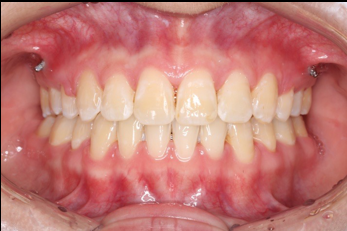

2018.11.14  术后磨牙尖牙I类关系,中线齐,覆合,覆盖正常

宏观评价:面部对称,面下三分一比例协调,上下唇凸度正常,上颌牙列内收转矩控制良好,下颌后缩改善,颏唇沟变得更加柔和,术后达到基本直面型。

迷你观评价:上下牙齿中线与面中线对齐,笑弧协调,微笑时牙龈暴露量正常,微笑时横向正常,左右唇基本对称。

微观评价:牙齿整齐,咬合关系良好,上下前牙转矩及突度控制良好,磨牙关系I类,尖窝咬合关系良好,OB,OJ正常。